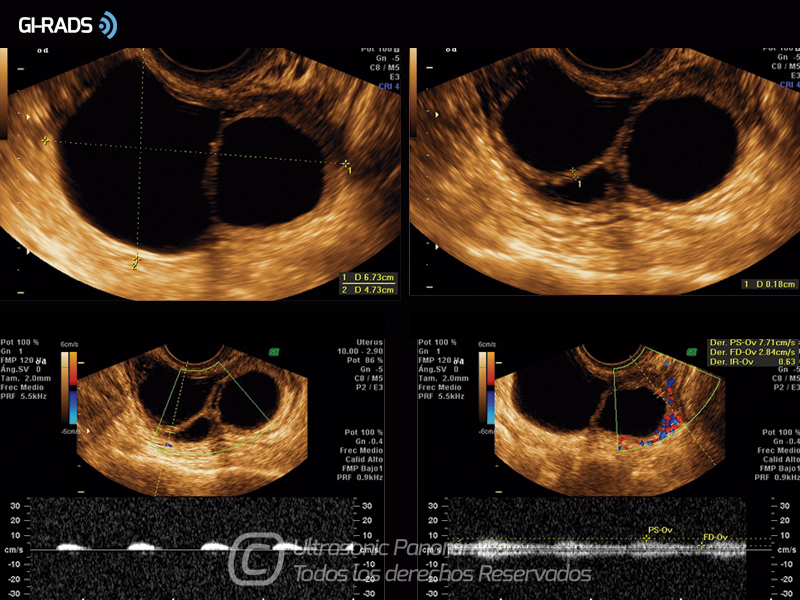

• Patologías Benignas – Cistoadenoma